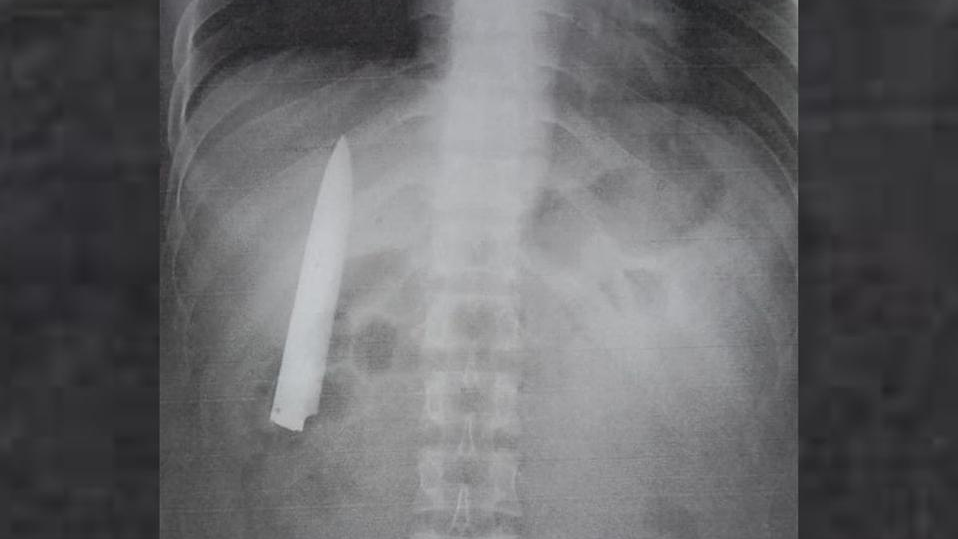

Un hombre se llevó la sorpresa de su vida cuando encontró una hoja de cuchillo dentro de su pecho, la cual estuvo ahí por más de un año, cuando fue apuñalado por un grupo de adolescentes en Filipinas. ¿Cómo no se dio cuenta antes? Te contamos los detalles.

Kent Ryan Tomao, un joven de 25 años originario del país asiático, fue llevado al hospital en enero de 2020 después ser atacado por los delincuentes. Al llegar, el médico y la enfermera no lo examinaron y sólo suturaron la herida, sin realizar una radiografía.

"No me tomaron ninguna radiografía. Simplemente lo cosieron recto porque el médico dijo que la herida era mínima. Siempre me pregunté por qué sentía algo de dolor en mi pecho cuando el clima era frío, pero no tenía idea de que elcuchillo seguía ahí", dijo el hombre al portal filipino ABS-CBN.

El joven filipino descubrió que durante 14 meses tenía una hoja de cuchillo dentro de su torso cuando asistió el pasado 23 de marzo a un hospital para realizarse pruebas de rayos X. Esto como requisito para postularse a un nuevo empleo en la provincia de Agusan del Sur.